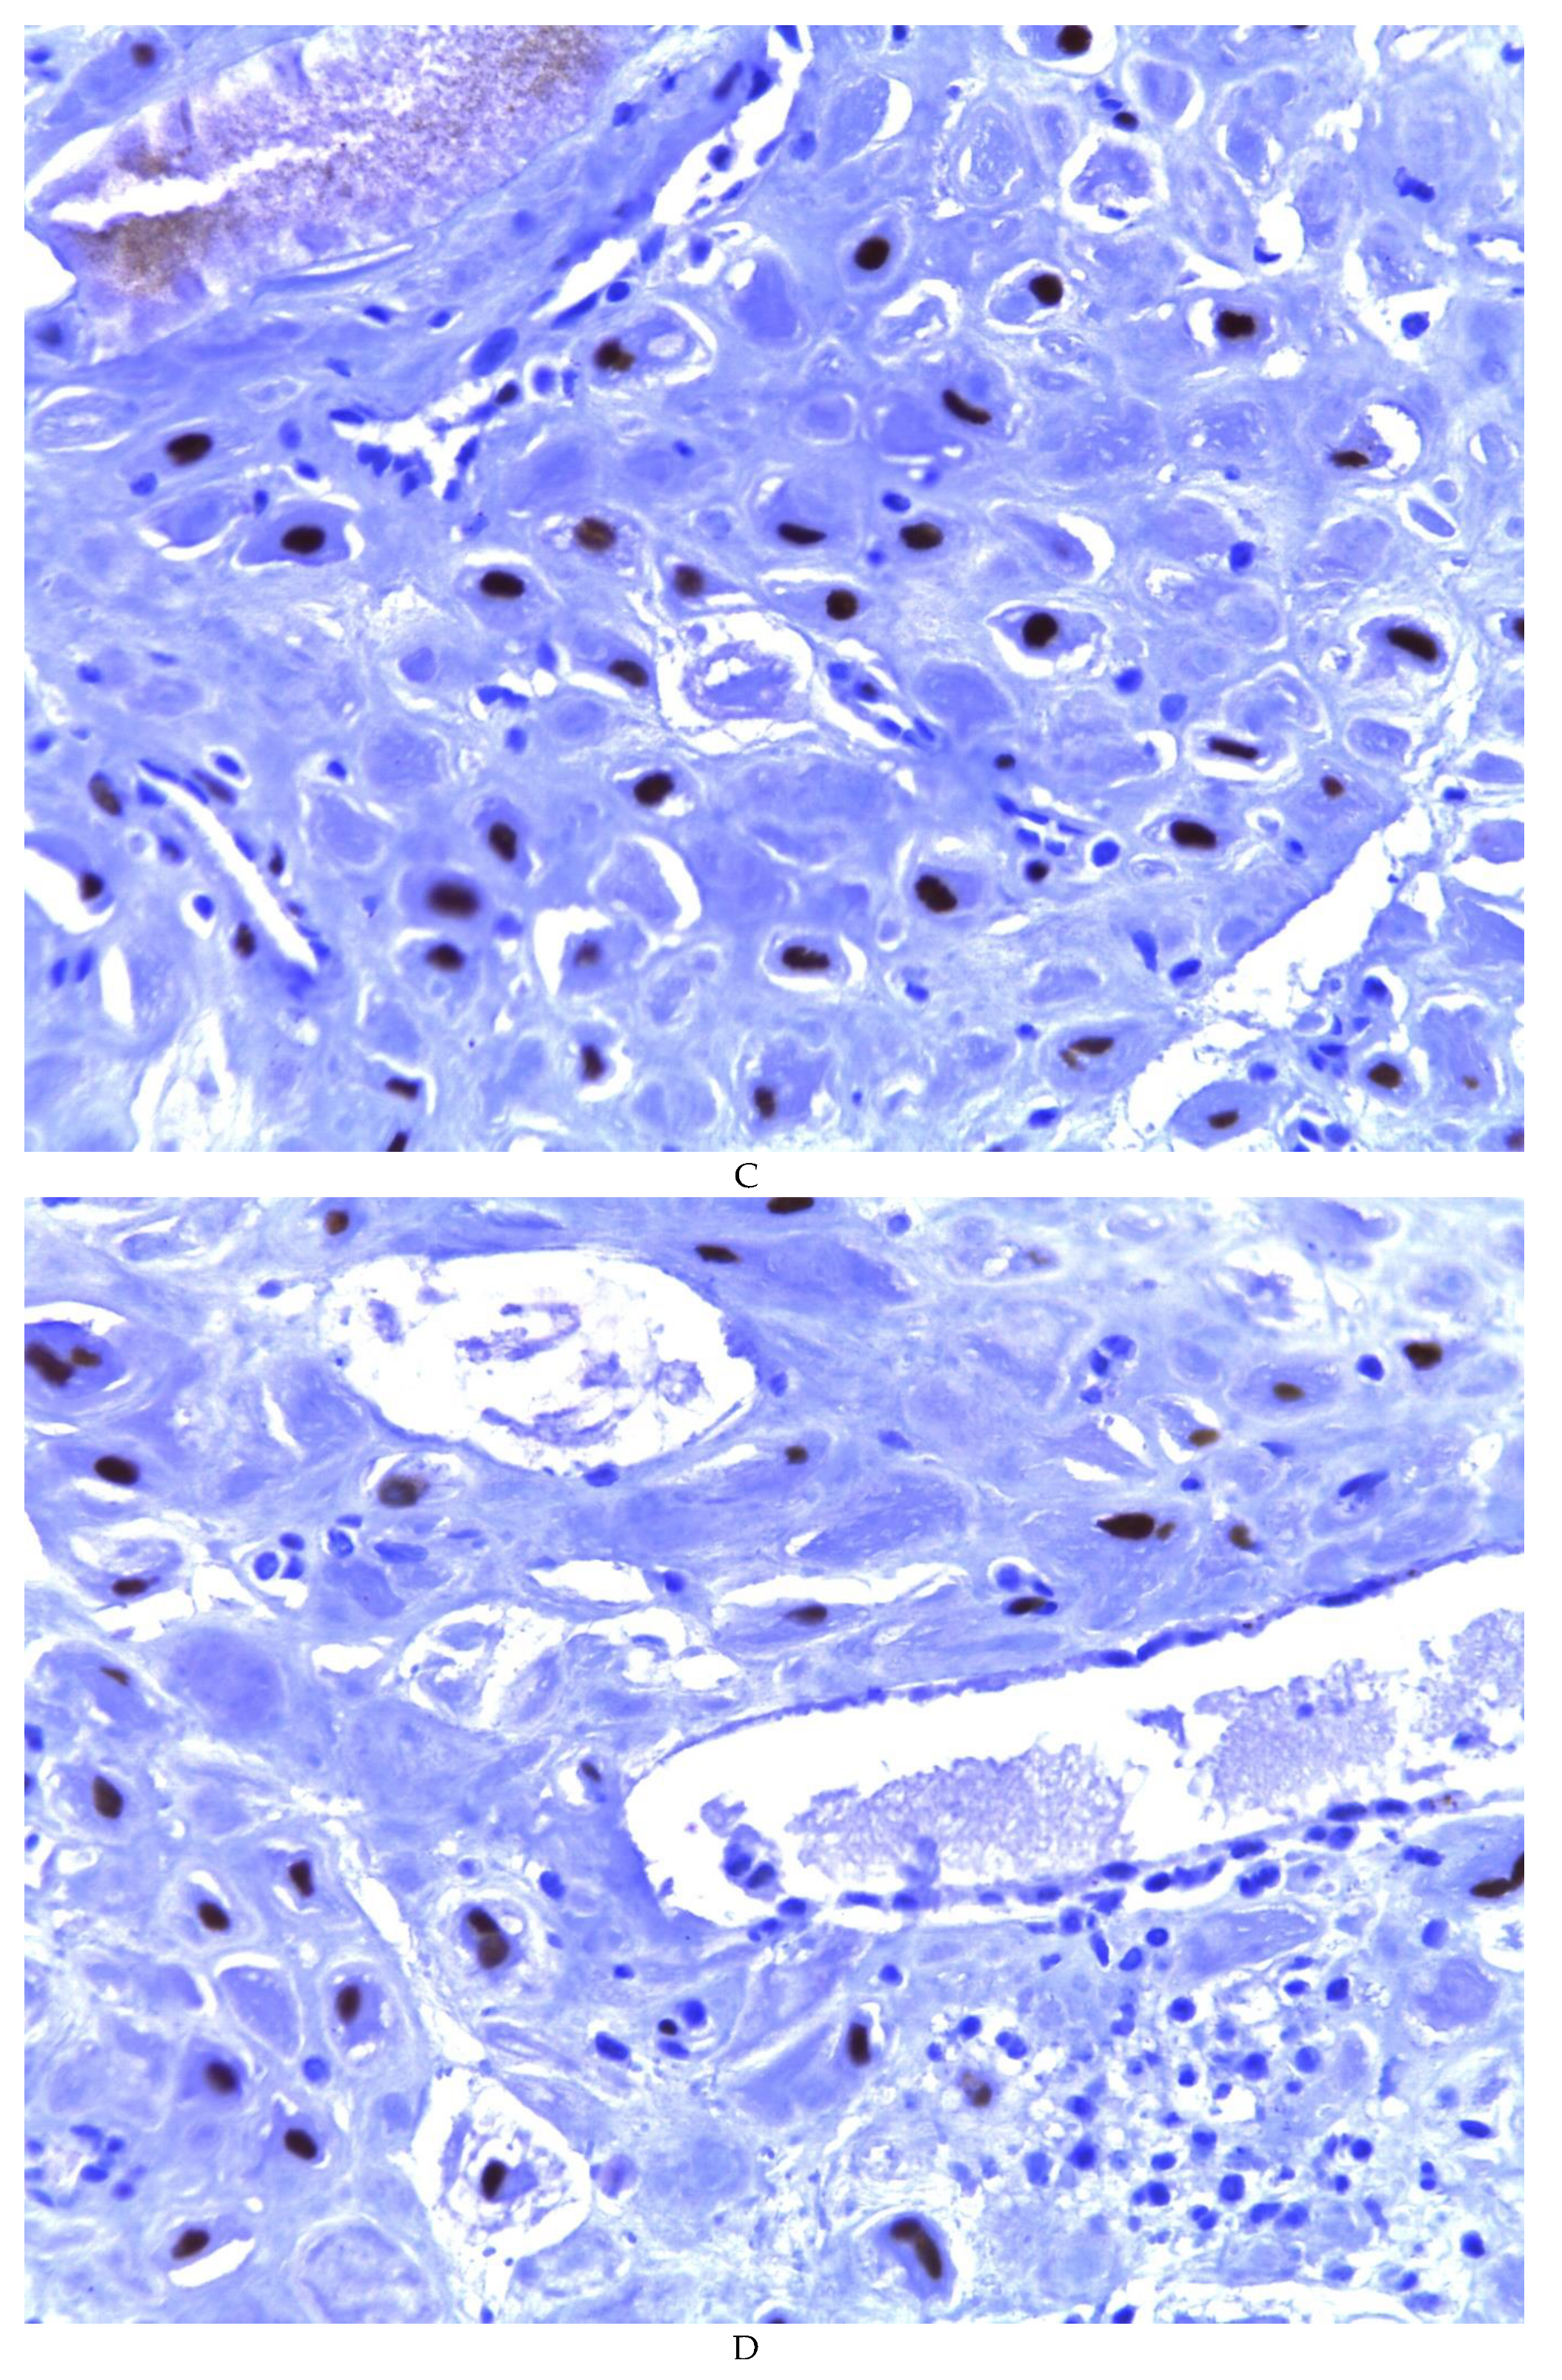

776 cases of endometriosis were collected between the two institutions participating in the study, in different anatomical sites (Table 1, Figure 1), in which 54 of them presented a myxoid stroma greater than 50% with respect to the cellularity of the samples. and that represent 6.95% of the total endometriosis examined with the following locations: omentum (4/20), ileum (2/4), ovary (14/216), parametria (2/9), soft tissues (28/235), salpingus (3/77), bladder (1/4). The clinical records of these patients were consulted and the common denominator was that the women were in the surgical (41/57) or physiological (7/39) puerperium in a period of time from 24 hours postpartum to six months after said event. Macroscopically, two different lesions were observed: the first one, which is the most frequent, presents as a non-encapsulated lesion with pushing edges of a fibromyxoid appearance; the second and less frequent, a well-defined lesion, partially or totally encapsulated, the cut surface is shiny, gelatinous in appearance, multilobed, light brown to brown in color with focal areas of recent and old hemorrhage, these lobes are separated by fibrous septa (Figure 2). Histologically, it was found in all the samples evaluated at least 50% of myxoid stroma with some fine connective tissue septa with proliferation of stromal cells (Figure 3A), which present four variants in their shape: (1) Epithelioid stromal cells of wide eosinophilic cytoplasm with round nucleus with small nucleolus (Figure 3B), (2) Pseudolipoblast-type stromal cells with moderate cytoplasm, multivacuolated in their cytoplasm that can present eosinophils or be clear cytoplasm, with central nuclei of granular chromatin (Figure 3C), (3) “pseudosignet ring” stromal cells with nucleus and cytoplasm rejected to the periphery giving the aforementioned appearance (Figure 3D) and (4) immersed spindle cells with small nucleus and barely visible nucleolus (Figure 3E); Among these cells, the epithelial component is observed, which is forming tubules that vary in diameter, ranging from small tubules and large cystic dilations of the gland that presents a layer of low cubic to cylindrical epithelium, generally with an atrophic appearance (Figure 3F). Hyaline globules were found in the glandular lumens (Figure 3G). The extracellular matrix showed a composition by glusocaminoglycans evidenced in 100% of the cases by staining present for AA (Figure 4A–C), but without staining for PAS; however, the latter stained on proteinaceous globular material in the lumen of the endometrial glands (Figure 4D). Immunohistochemistry for CD10 was positive in 100% of the stromal cells with a mild to moderate reaction in the cytoplasm and membrane with a decidual appearance (Figure 5A,B). The ER and PR showed nuclear expression in 100% of the cases, with greater intensity in the ER (Figure 5C) than in the RP (Figure 5D); both hormone receptors were expressed on endometrial epithelial cells as well as on stromal cells. The cases of myxoid endometriosis examined did not present cytological atypia suggesting any precursor lesion of epithelial or stromal origin.

Figure 5. Myxoid endometriosis - immunohistochemistry: A-B) CD10. C) Estrogen receptor. DE) Progesterone receptor.